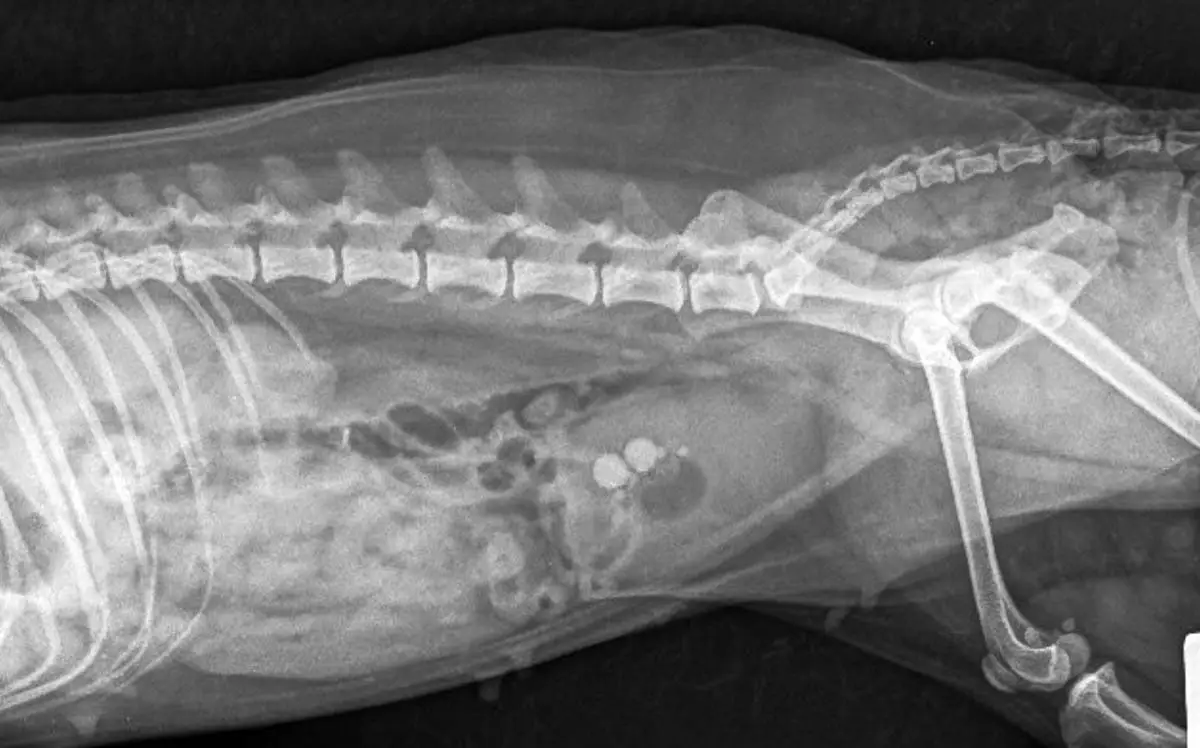

- x -raggi O Ultrasond: لتحديد معظم الحجارة ، سيظهر هذا أيضًا موقع وحجم الحجارة.